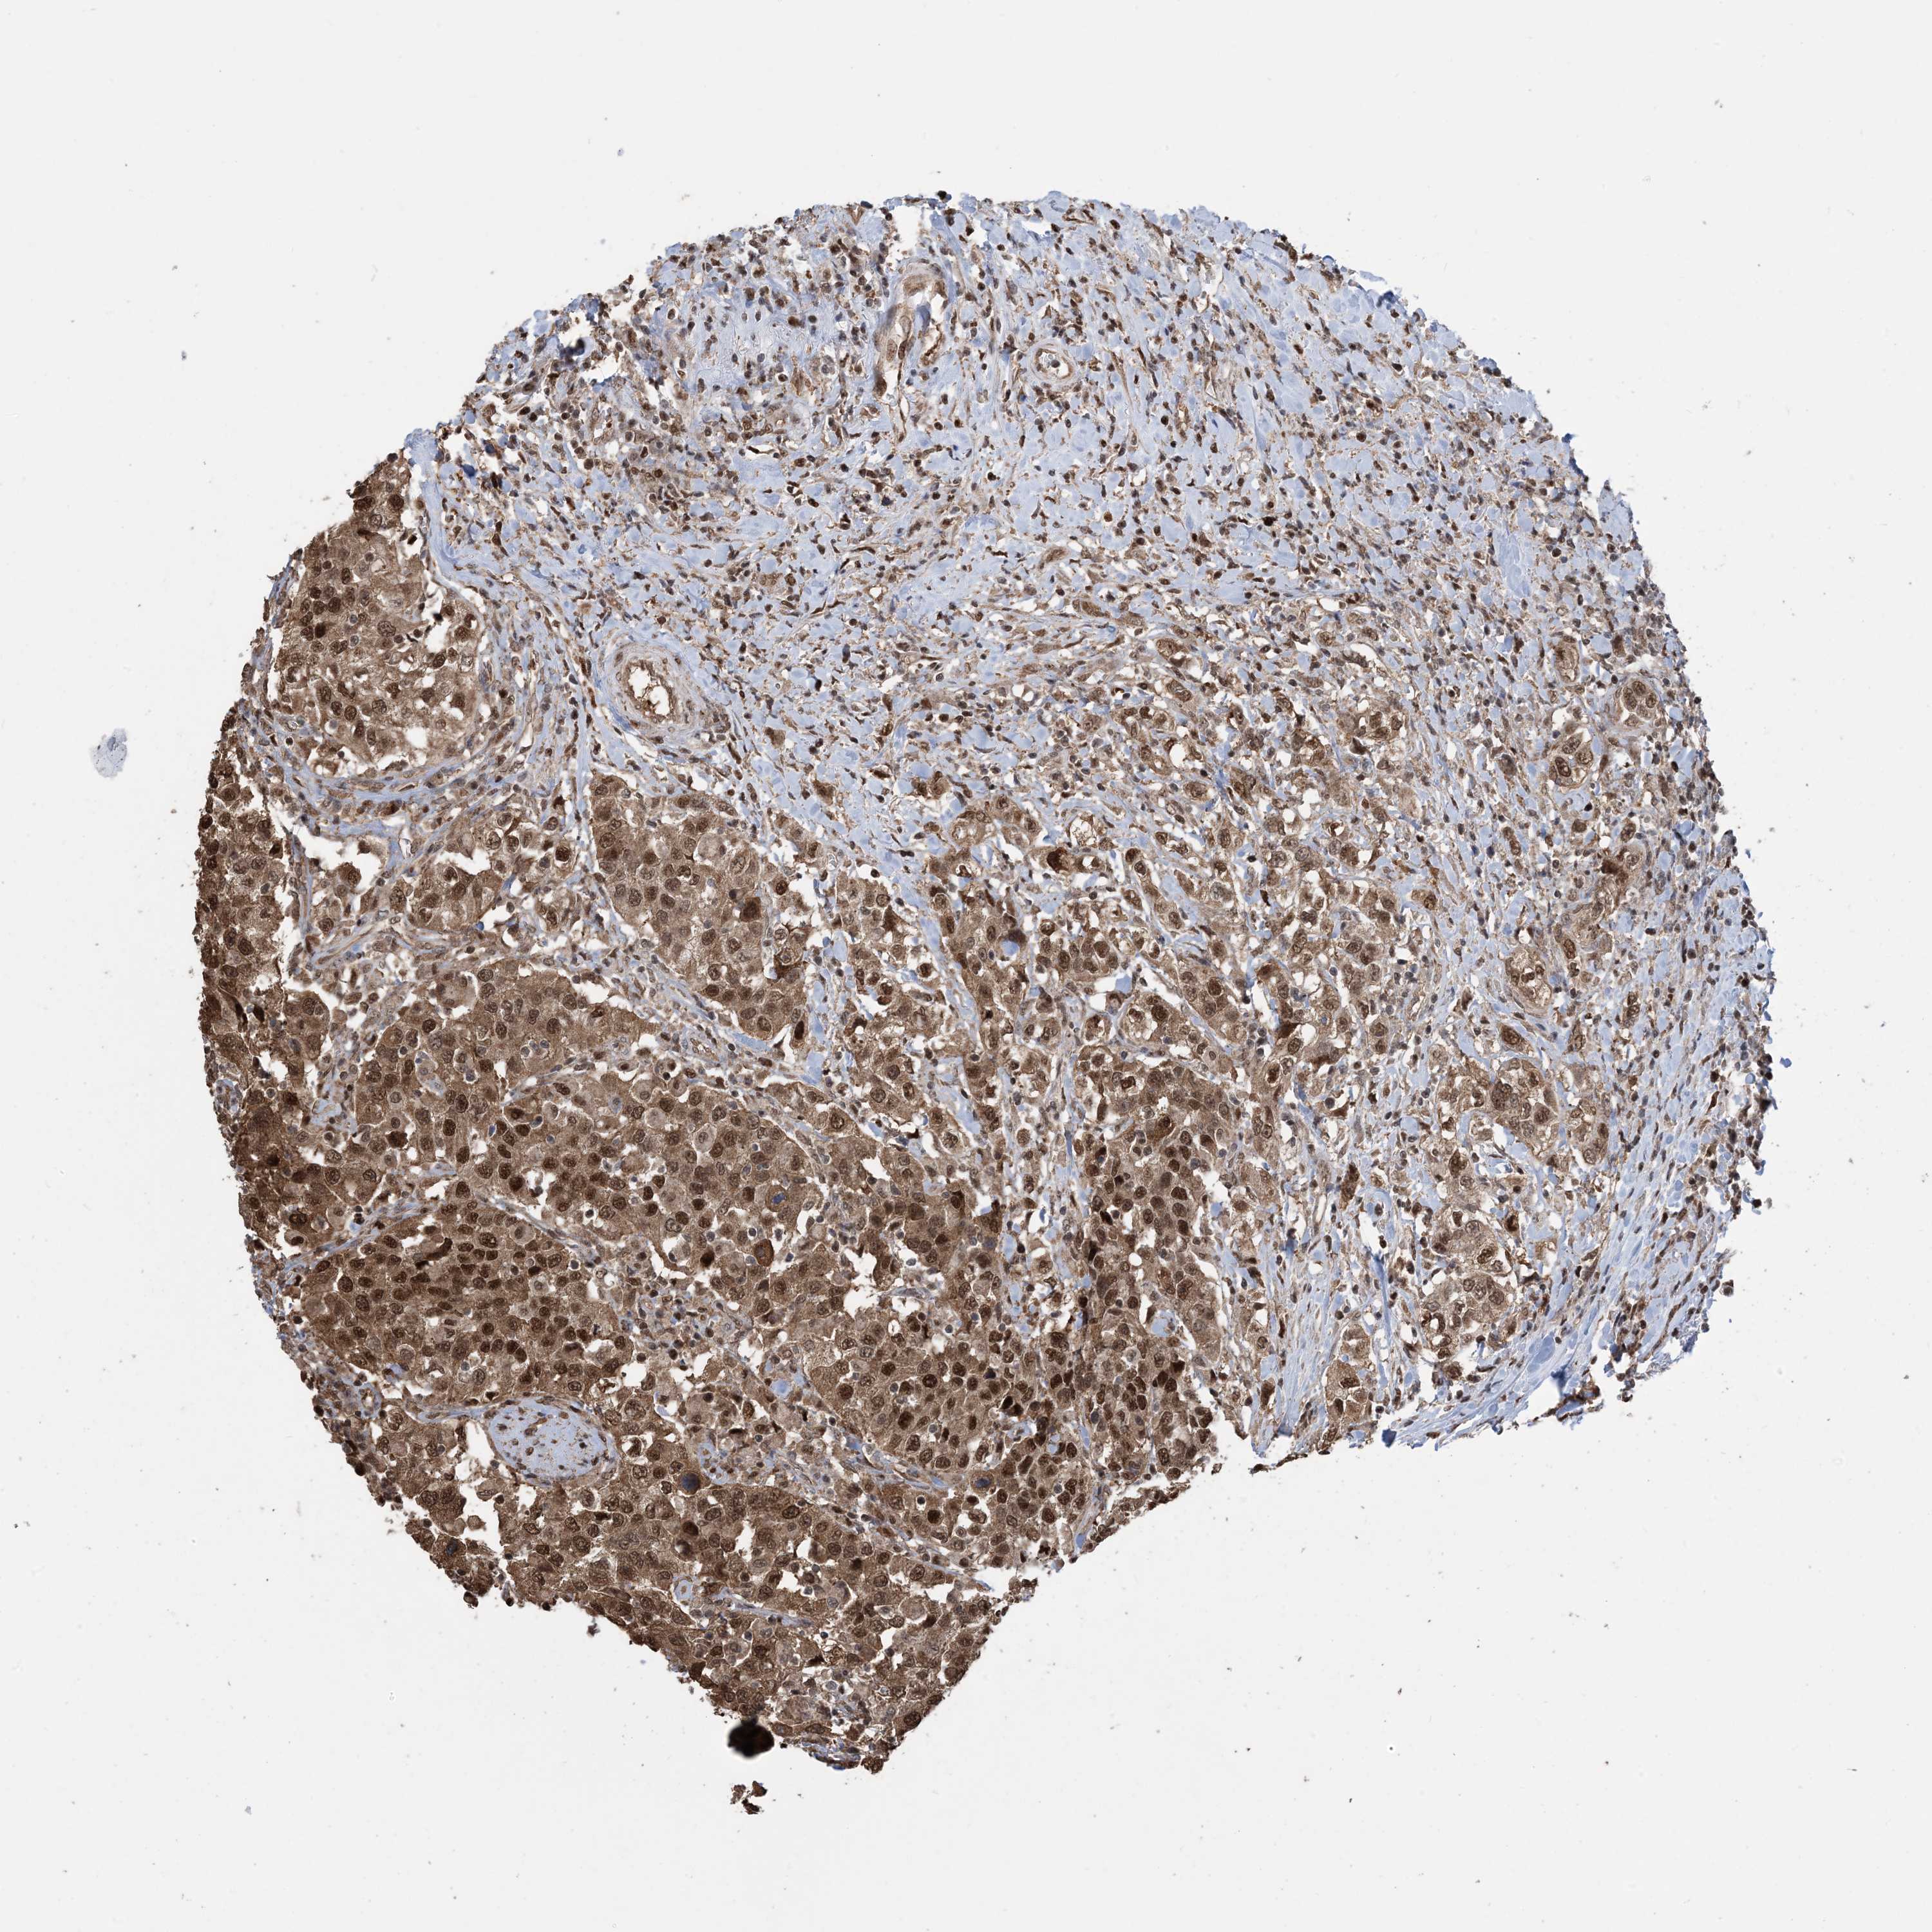

UROTHELIAL CANCER - Protein expressioni

A mouse-over function shows sample information and annotation data. Click on an image to view it in a full screen mode. Samples can be filtered based on level of antibody staining by selecting one or several of the following categories: high, medium, low and not detected. The assay and annotation is described here.

Note that samples used for immunohistochemistry by the Human Protein Atlas do not correspond to samples in the TCGA dataset.

Antibody stainingi

Antibody staining in the annotated cell types in the current human tissue is reported as not detected, low, medium, or high, based on conventional immunohistochemistry profiling in selected tissues. This score is based on the combination of the staining intensity and fraction of stained cells.

Each image is clickable and will lead to virtual microscopy that enables deeper exploration of all samples and also displays staining intensity scores, fraction scores and subcellular localization as well as patient and tissue information for each sample.

Antibody HPA052504

Antibody CAB017451

Antibody CAB032815

Staining

High

Medium

Low

Not detected

Intensity

Strong

Moderate

Weak

Negative

Quantity

>75%

75%-25%

<25%

None

Location

Nuclear

Cytoplasmic/membranous

Cytoplasmic/membranous,nuclear

Urothelial carcinoma, High grade

Urothelial carcinoma, NOS

Urothelial carcinoma, Low grade